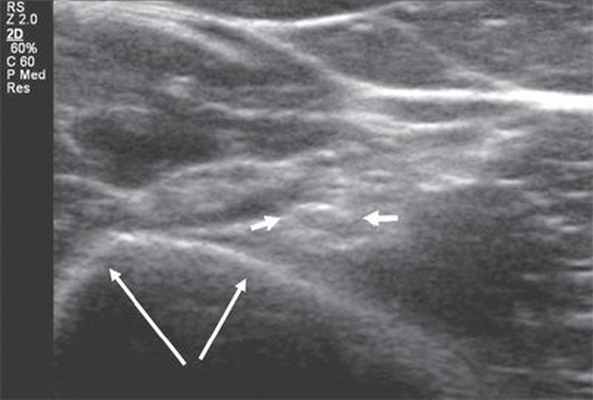

Ультразвуковая анатомия периферических нервов в норме

Для ультразвуковых исследований используются датчики с частотой 7-17 МГц, но в некоторых случаях необходимо применение трансдьюсеров с более низкой частотой - 3-5 МГц. В процессе сканирования оценивают анатомическую целость нервного ствола, его структуру, четкость контуров нерва и состояние окружающих тканей. Все перечисленные пункты выше нужно обязательно отражать в протоколе исследования. В случае выявления патологических изменений в структуре нерва указывают вид повреждения (полное или частичное), зону и степень компрессии нервного ствола (отмечают уменьшение диаметра нерва и причину сдавления). При обнаружении объемного образования описывают его размеры и структуру, контуры, взаимоотношение с окружающими мягкими тканями, наличие или отсутствие кровотока.

Ультразвуковое исследование периферических нервов целесообразно начинать с поперечной проекции в точке, где нервный ствол легче всего идентифицировать, смещаясь затем в проксимальном и дистальном направлениях, оценивая структуру нерва на протяжении 3.

Изображение нерва имеет ряд характерных признаков. В поперечной проекции он выглядит как овальное или округлое образование с четким гиперэхогенным контуром и внутренней гетерогенной упорядоченной структурой ("соль - перец", "медовые соты") [4, 6, 7]. В продольной проекции нерв лоцируется в виде линейной структуры с четким эхогенным контуром, в составе которой правильно чередуются гипо- и гиперэхогенные полосы - "электрический кабель" [7]. Толщина периферических нервов вариабельна и составляет от 1 мм для пальцевых нервов до 8 мм для седалищного нерва.

Рис. 1. Поперечная сонограмма лучевого нерва (короткие стрелки) на уровне спирального канала плечевой кости (длинные стрелки - контур плечевой кости).